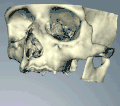

Планирование

При планировании зубных имплантатов основное внимание уделяется общему состоянию здоровья пациента, местному состоянию здоровья слизистых оболочек и челюстей, а также форме, размеру и положению костей челюстей, соседних и противолежащих зубов.